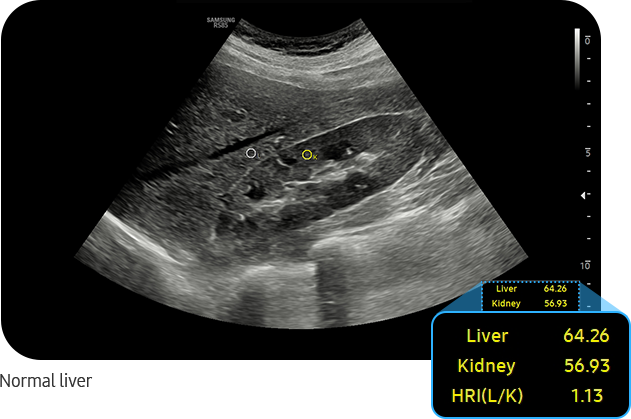

EzHRI™ places 2 ROIs on the liver parenchyma and renal cortex and provides HRI* ratio. It offers convenience and an improved workflow by suggesting initial ROIs, calculates the average brightness ratio of the liver parenchyma and the renal cortex.